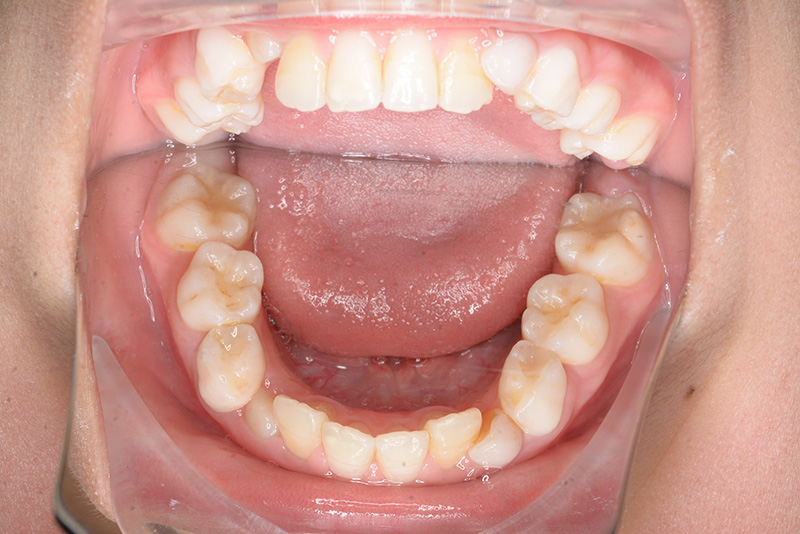

| 批評・予后 | 早期に6の遠心移動を行いナンスのホールディングアーチにて保隙をした結果、5は良好な状態で萌出できたように思う。 今後は永久歯列完成まで経過観察を行っていく予定である。 |